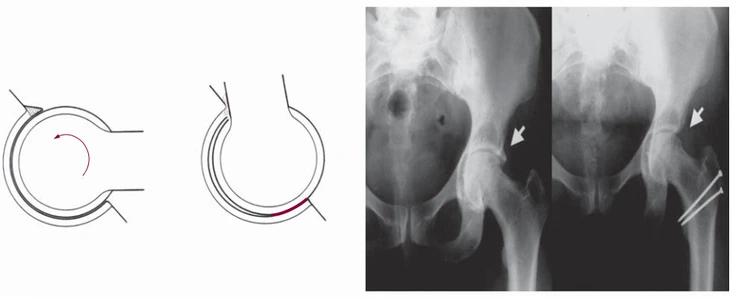

#1. Can Impingement

대퇴-비구 충돌중후군은 대퇴와 비구사이의 충돌입니다. Cam 충돌은 대퇴골두의 문제로 발생하는 충돌증후군입니다. 대퇴골두가 비정상적으로 직경이 커지거나, 뾰족한 부분이 생기는 경우에 발생합니다. 특히 고관절을 앞으로 굽힐 때 (고관절 굴곡시) 많이 발생합니다. 커진 대퇴골두나 대퇴 근위부의 융기는(Prominence) 비구순(Labrum)을 손상하게 됩니다. 위의 사진에 우측 X-ray를 보면 대퇴골두가 경부와 만나는 곳에서 융기되어 있습니다. 이 부분이 고관절의 움직임(특히 굴곡)에 의해 지속적인 자극을 주면 비구순(Labrum)이 찢길 수도 있고, 관골구 개연(Rim of Acetabulum)이 손상되기도 합니다. 심지어 관골구(Acetabulum)의 골연골을 박리하기도 합니다.

X-ray상에서는 대퇴골두나 대퇴골근위부에서 튀어나온 융기부분을 확인할 수 있습니다. 그러나 대퇴골두부분의 경우 단순 AP view에서는 정확하게 융기부가 보이지 않는 경우가 많습니다. 이럴 때에는 20도 정도 외전방향에서 촬영을 해야 대퇴골두부분을 더 정확히 확인할 수 있습니다. 이런 촬영방식을 불러 Modified Dunn view라고 합니다. A의 경우 대퇴골두에서 경부로 이어지는 부분이 움푹 들어가 정상적인 모습을 보이지만, 약간만 방향을 틀어 B의 영상(Modified Dunn view)을 얻으면 융기된 부분을 찾아낼 수 있습니다.